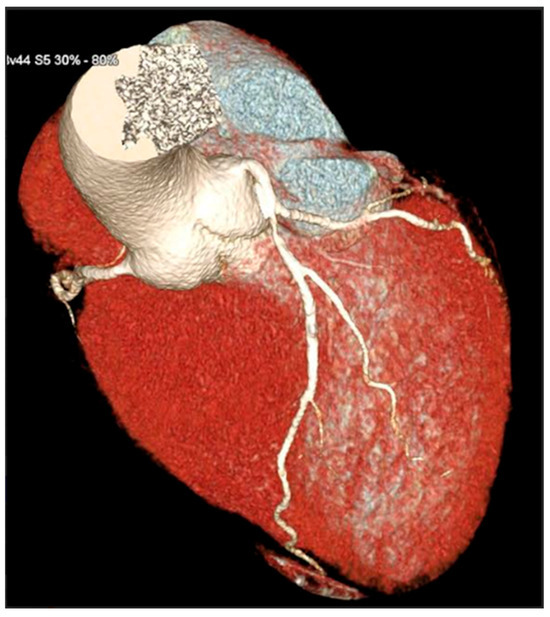

Figure 3.

3D reconstruction of coronary CT angiography showing a significant stenosis in the proximal segment of the left anterior descending coronary artery.

High-risk plaque features were assessed and included low-attenuation plaque (LAP, ≤30 HU), spotty calcification (SC, dense foci > 130 HU within non-calcified tissue and <3 mm), and positive remodeling (PR, remodeling index ≥ 1.1) (Figure 4).

Figure 4.

Coronary CT angiography showing different plaques and morphologies along different coronary arteries. (A,B) show predominantly non-calcified plaque, with low density, positive remodeling, and spotty calcification; (C) shows several predominantly calcified plaques all along coronary arteries, mainly the left anterior descending artery.